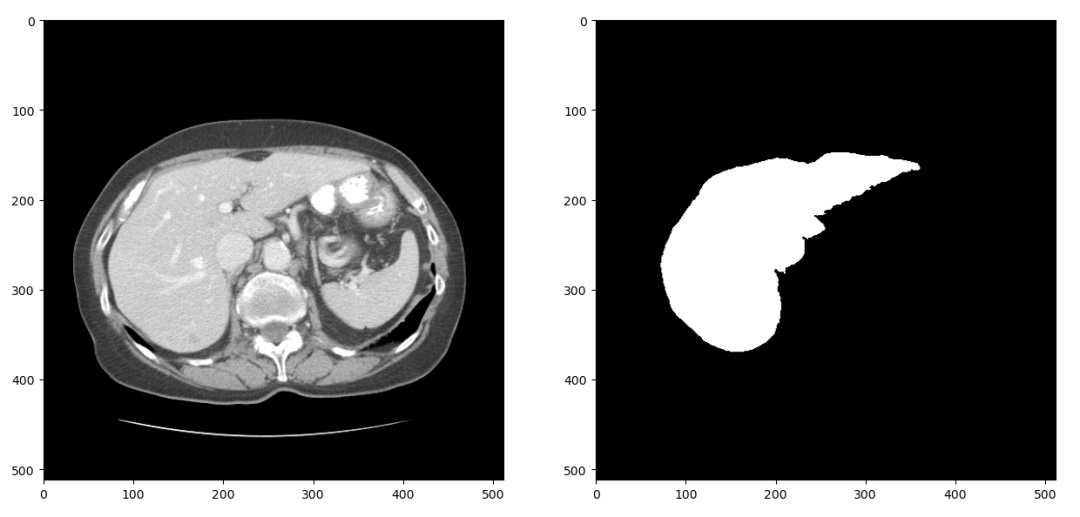

上述的Res-Unet结构是一个2D的分割网络,因此我们首先将LiTS数据集中3D的CT扫描分成2D的切片。CT在拍摄和重建的过程中会引入一些噪声,因此我们只保留-1024到1024范围内的数据。经过这两步处理,可以得到大概1万张CT扫描切片及对应的分割标签,随机选择一组进行可视化结果如下:

图4 2D切片在训练 深度神经网络 的过程中,我们通常需要在训练集上训练多个epoch以让网络达到一个比较高的训练 准确率 。但是这样做又容易使网络 过拟合 训练集,其表现为网络在训练集上 准确率 很高但是测试时 准确率 偏低。针对这个问题有多方面的解决方案,数据增强是其中重要的一种。这个项目中我们采用的数据增强策略包括随机水平、垂直翻转、随机旋转、随机尺度缩放、随机位置裁剪和弹性形变。在项目中可以看到具体代码,图5是对图4中数据进行数据增强的结果: